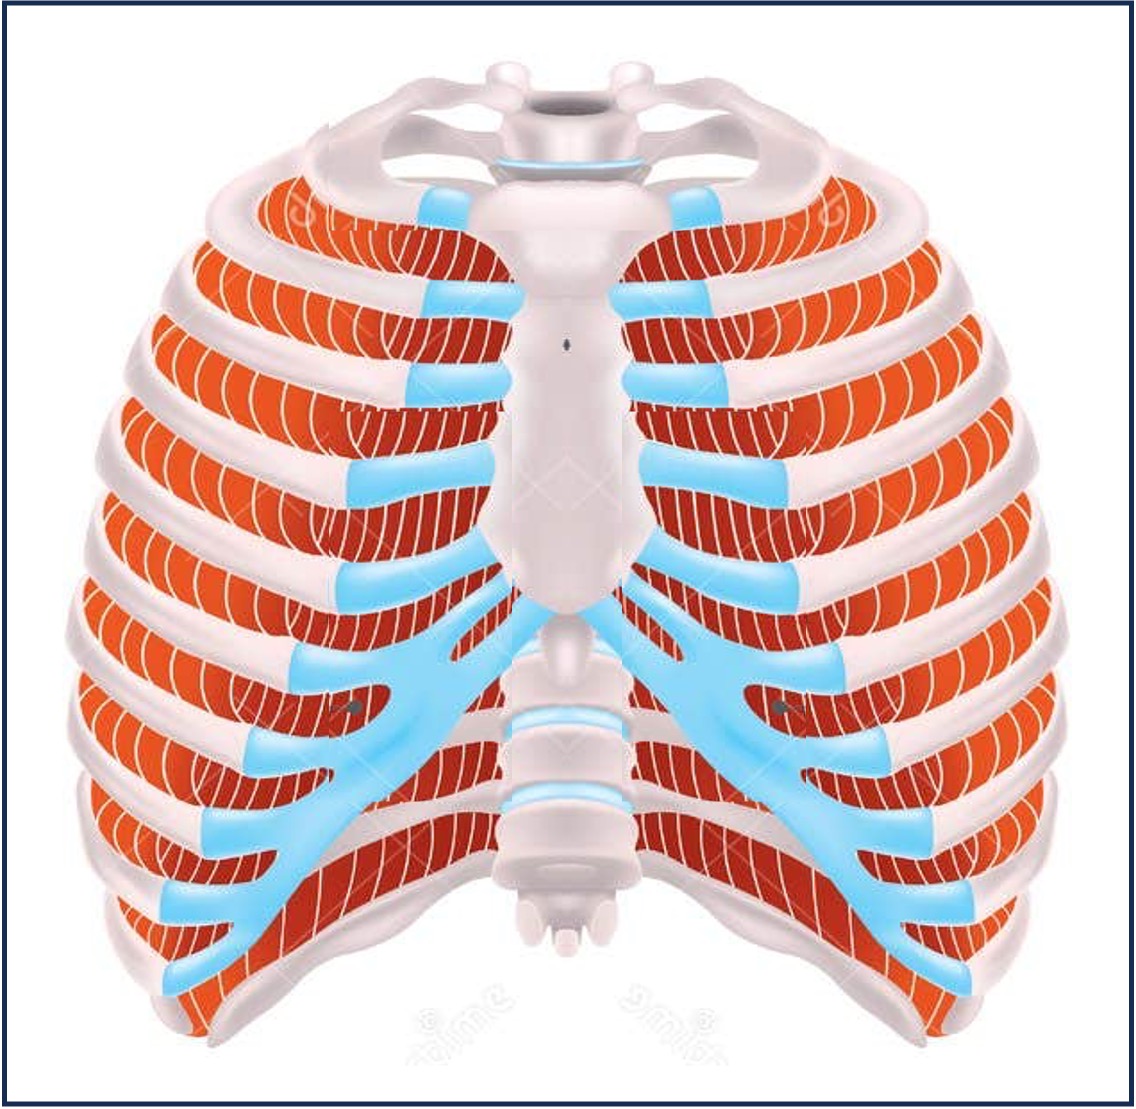

Intercostal Muscles

The muscles responsible for inspiration are the diaphragm and external intercostals (plus some accessory muscles)

The muscles responsible for expiration are the abdominal muscles and internal intercostals (plus some accessory muscles)

External intercostals contract, pulling ribs upwards and outwards (expanding chest)

Internal intercostals contract, pulling ribs downwards and inwards (constricting chest)